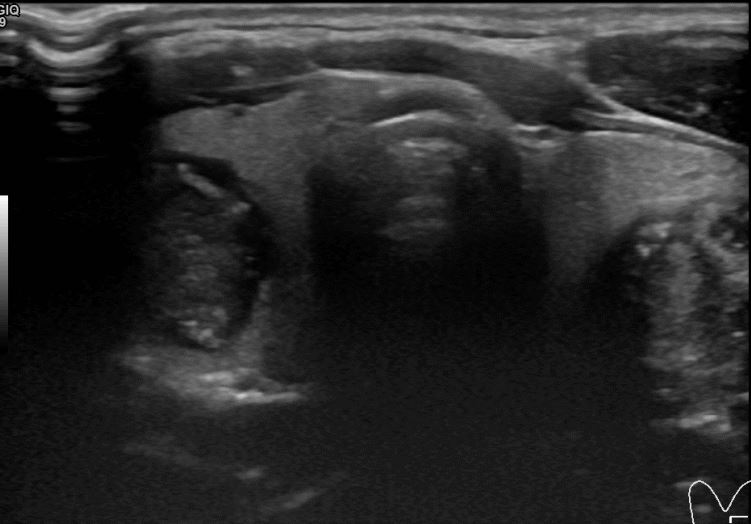

상기환자 외부검진이후 세침검사위해  내원하신 30대초반 여성분으로 의심스러운 좌엽혹 세포검사진행후 갑상선암으로 진단되었습니다